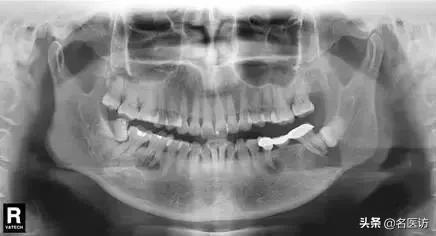

相信大部分的人和小编一样,没等看到具体病情就已经被图中这个巨大的“球”状物体吓到。小小的下巴竟能长出这么大的“球”!

“患者是30多岁的年轻男子,红色标记那颗牙松动,要求拔牙,开始嫌麻烦不愿拍片,后来经过再三劝说还是拍了片。结果把所有人包括他自己都吓了一跳。估计是良性,具体还得去医院住院手术做病理检查,所以大家不要忽视一张片子带来辅助检查的重要性。”

试想,如果没有拍片,直接贸然拔牙,一旦出现问题......

一张牙片,“救了”诊所,也“救了”患者!